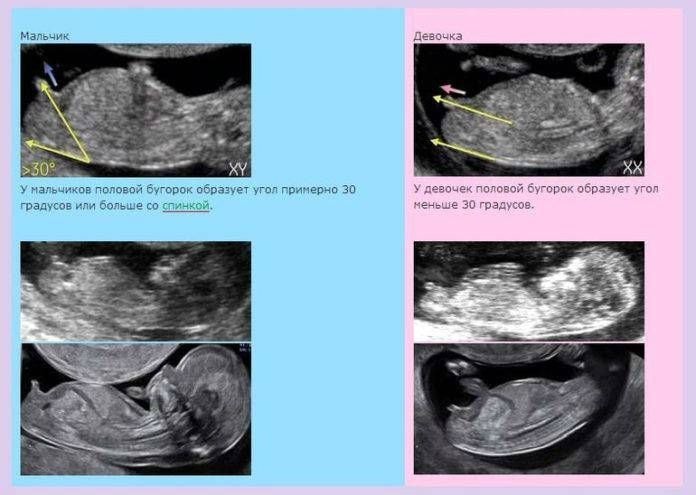

Анна Яновская, спинка согнута. Смотрят угол между половым бугорком и позвоночником. Если спинка согнута, то может быть не оч достоверно

Пол ребенка Пол малыша